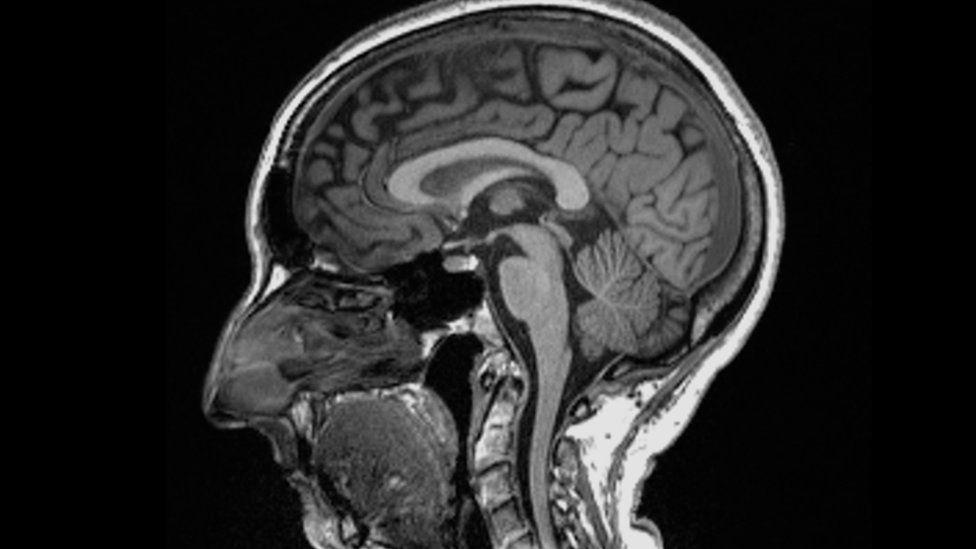

Scientists found significant differences in MRI (magnetic resonance imaging) scans before and after infection.

Even after a mild infection, the overall size of the brain had shrunk slightly, with less grey matter in the parts related to smell and memory.

The overall brain size in infected participants had shrunk between 0.2 and 2%

There were losses in grey matter in the olfactory areas, linked to smell, and regions linked to memory

The most significant loss of grey matter was in the olfactory areas – but it is unclear whether the virus directly attacks this region or cells simply die off through lack of use after people with Covid lose their sense of smell.